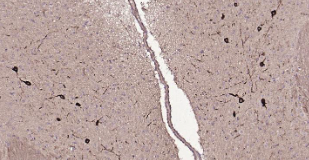

Immunohistochemical analysis of paraffin embedded mouse brain tissue slide using IHC0220M (Mouse Tyrosine Hydroxylase IHC Kit).